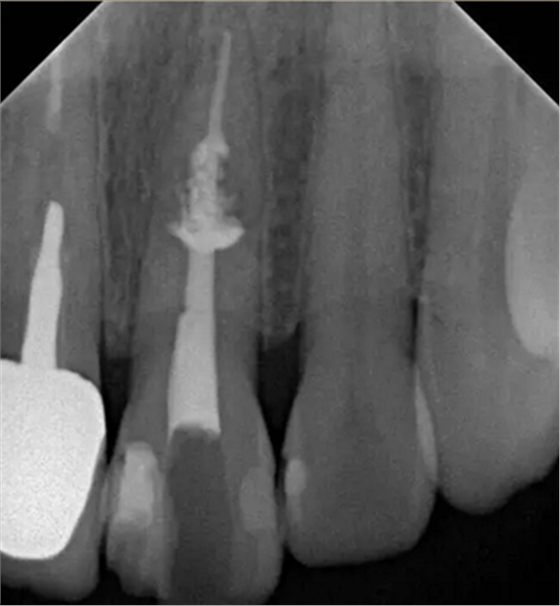

診斷:左上中切牙牙根內(nèi)吸收。治療計劃:左上中切牙根管治療,全冠修復。 治療過程:患者知情同意。使用含1/100,000腎上腺素的4%鹽酸阿替卡因(碧蘭麻,艾龍)局部浸潤麻醉,橡皮障隔濕。去腐未盡露髓,露髓孔出血多。開髓,使用10#不銹鋼K銼(MANI,日本)探查根管,根管中段有鈣化物阻擋,不能達到牙根全長(圖3A)。在顯微鏡下(Leica M400E,萊卡, 德國) 使用超聲尖(E1根管治療超聲尖,啄木鳥公司,中國)通開,采用根管長度測量儀(Root ZX, Morita公司,日本)加診斷絲片法(圖1B)測量根管長22 mm。使用控制扭矩馬達(X-smart,登士柏)和鎳鈦旋轉器械(Hero 642, Micromega)根管預備,根管預備過程中使用5.25%次氯酸鈉溶液沖洗。 根備完成后使用超聲蕩洗根管,5.25%次氯酸鈉溶液3 分鐘, 17% EDTA溶液1分鐘。干燥根管,使用螺旋充填器根管內(nèi)封氫氧化鈣糊,氧化鋅丁香油水門汀暫封。1周后患者復診,患者述無術后不適,檢查暫封完好,無叩痛,不松,牙齦無紅腫瘺管。使用橡皮障隔濕,去除暫封物,超聲蕩洗根管,5.25%次氯酸鈉溶液3 分鐘, 17% EDTA溶液1分鐘。干燥根管,牙膠尖(達雅鼎,中國)和必蘭根充糊劑(Cortisomol, 艾龍公司,法國)熱垂直加壓法根管充填。術后片顯示根充恰填,可見牙膠/糊劑被壓入鈣化物周圍和內(nèi)部縫隙內(nèi)